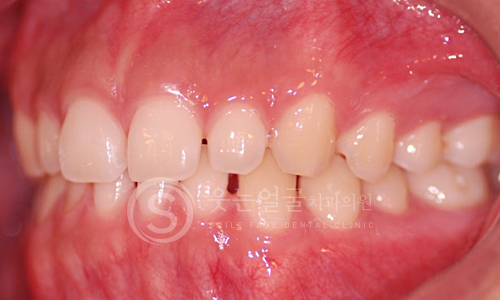

한눈에 보는

치아교정 전후사진